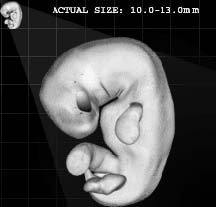

A Korán Allah szava, amelyet Mohammed Prófétának (Allah áldása és békéje Reá) küldött le a Földre Gábriel angyal segítségével. Mohammed Próféta (Allah áldása és békéje Reá) feladata volt, hogy átadja az Iszlám üzenetét az emberiségnek. A Korán így Allah egyik csodája, olvasása közelebb viszi a hívőket Urukhoz, s közbenjáró is lesz a hívőkért az Ítélet napján. A Korán csodás a történetei terén, minden korábbi írásnál sokkal teljesebb, pontosabb leírást ad a Paradicsomról és a Pokolról is, az egész Túlvilágról, a Feltámadás Napjáról, arról, hogy mi történik a halál után. Csodás a törvénykezés terén, az élet valamennyi területére nézve gyakorlati útmutatót is tartalmaz. Egyedülállóságát bizonyítja, hogy amikor még a kalifátus létezett, és egy állam vezetése is az Iszlám törvénykezésnek (Sariának) megfelőlen valósult meg, az az Iszlám fénykora volt, s az embereknek a legjobbat jelentette. Sajnos mára már egyetlen ország kormányzása sem e törvénykezés, azaz az isteni törvények alapján történik. A Korán csodás a tudományok terén is, számos olyan tényt tartalmaz, amelyet az egyes tudományokban csak jóval a kinyilatkoztatása után fedeztek fel. Például a fejlődéstanra vonatkozólag részletesen leírja a magzatfejlődést. Olyan dolgokat is megtalálhatunk benne, amelyeket később a csillagászatban, természettudományok terén fedeztek fel. E felfedezések összhangban vannak a Koránban leírtakkal. (Komáromi, 2005) Jónéhány tudós ezért vált muszlimmá, mert megvilágosodott előttük a Korán csodája a tudomány terén, s minden más tekintetben is.

9 Az ájának ez a része azt jelenti, hogy ha egy muszlim embernek a családtagját megölték és Iszlám bíróság előtt, bírósági per lefolytatása után a gyilkos vétkesnek bizonyult, akkor a legközelebbi hozzátartozó a gyilkos halálbüntetését kérheti. Ettől a jogától azonban el is állhat. Ez kizárólag Iszlám államban történhet meg és csak teljes bizonyosságot nyert gyilkosság esetén. Allah azonban azt is mondja a Koránban, hogy jobb ha a hozzátartozó illetve a család megbocsát inkább a gyilkosnak és nem kérik a halálbüntetését. Ez a törvény leginkább elrettentésül szolgál, azért hogy minden hívő illetve nem hívő is tudja, hogy az emberölésnek mekkora súlya van és meg se forduljon a fejében egy ilyen tettet elkövetni. Illetve, hogy annak, akinek mégis ilyen szándéka van, azt visszatartsa ez a törvény ettől a tettől. Egy hívő embernek azonban nyilvánvalóan nem lehet soha ilyen szándéka, de még gondolata sem.